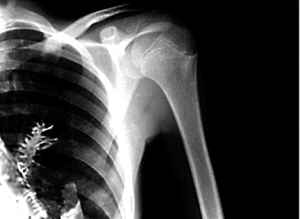

用X射线成像技术拍摄物体